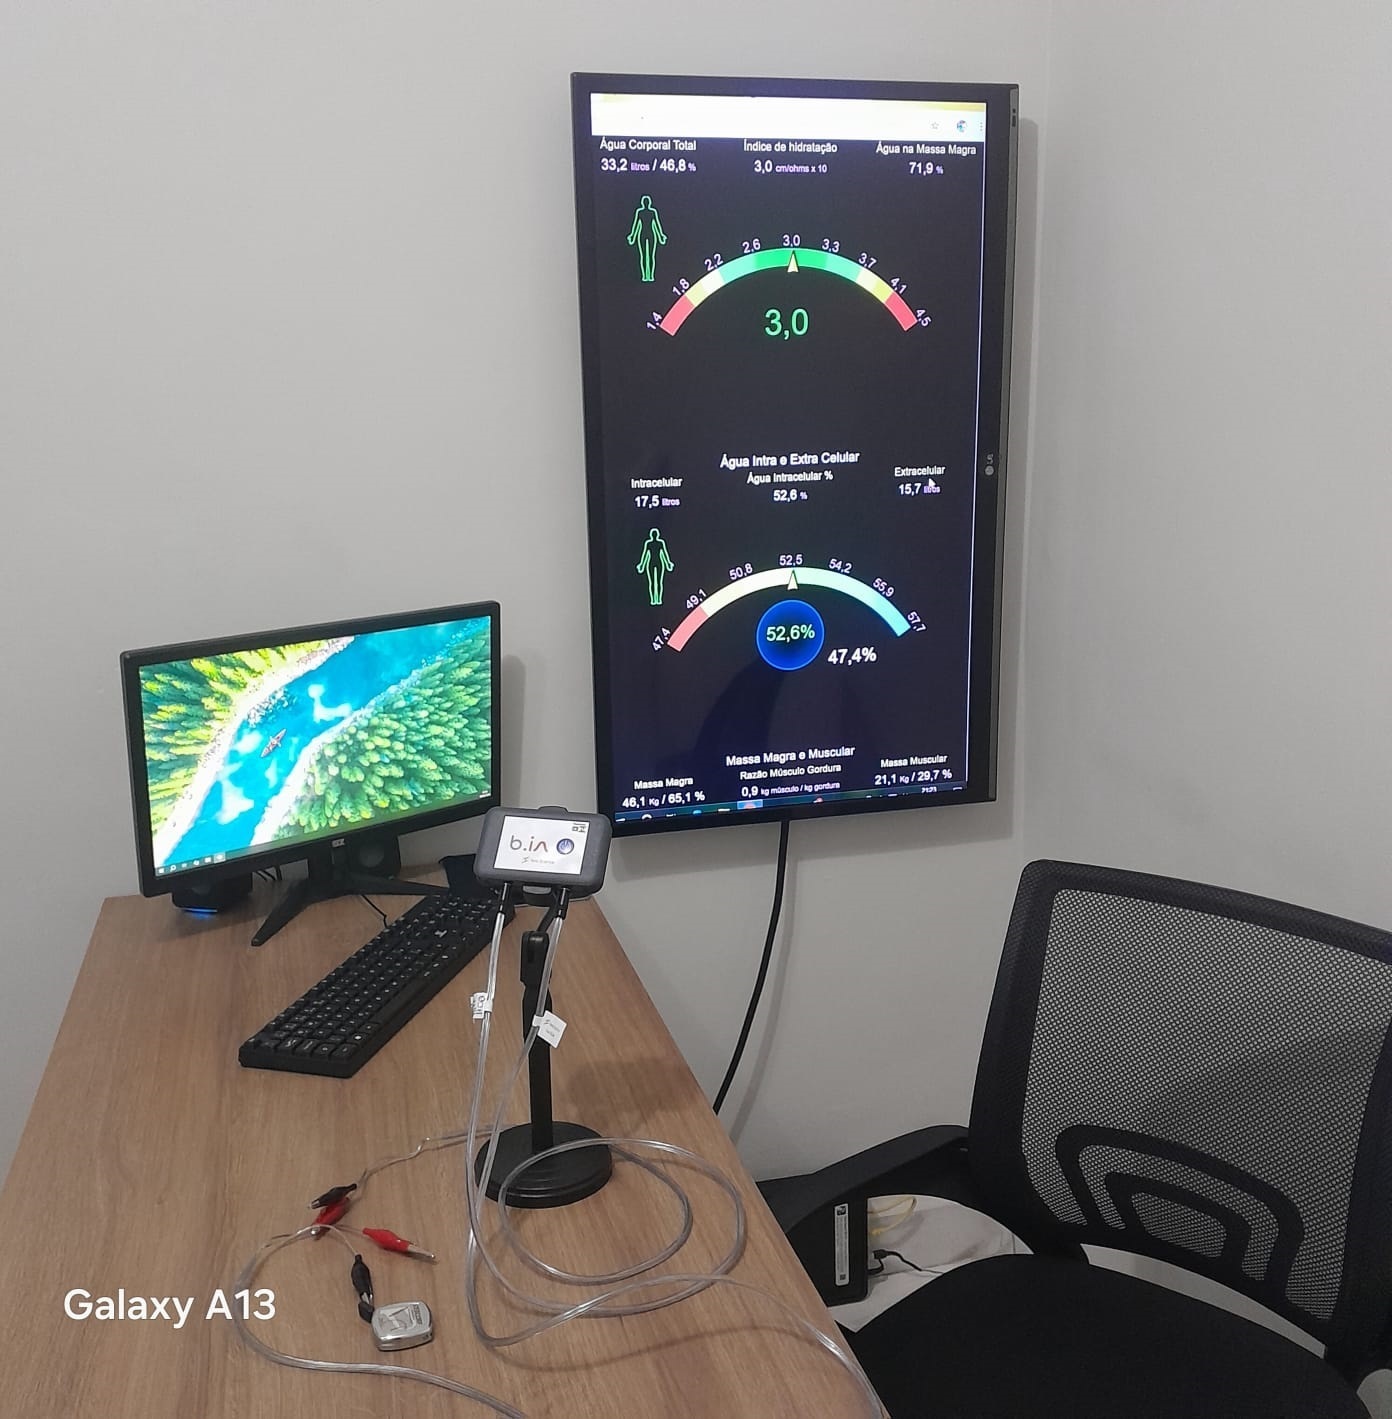

Hidratação intra e extracelular